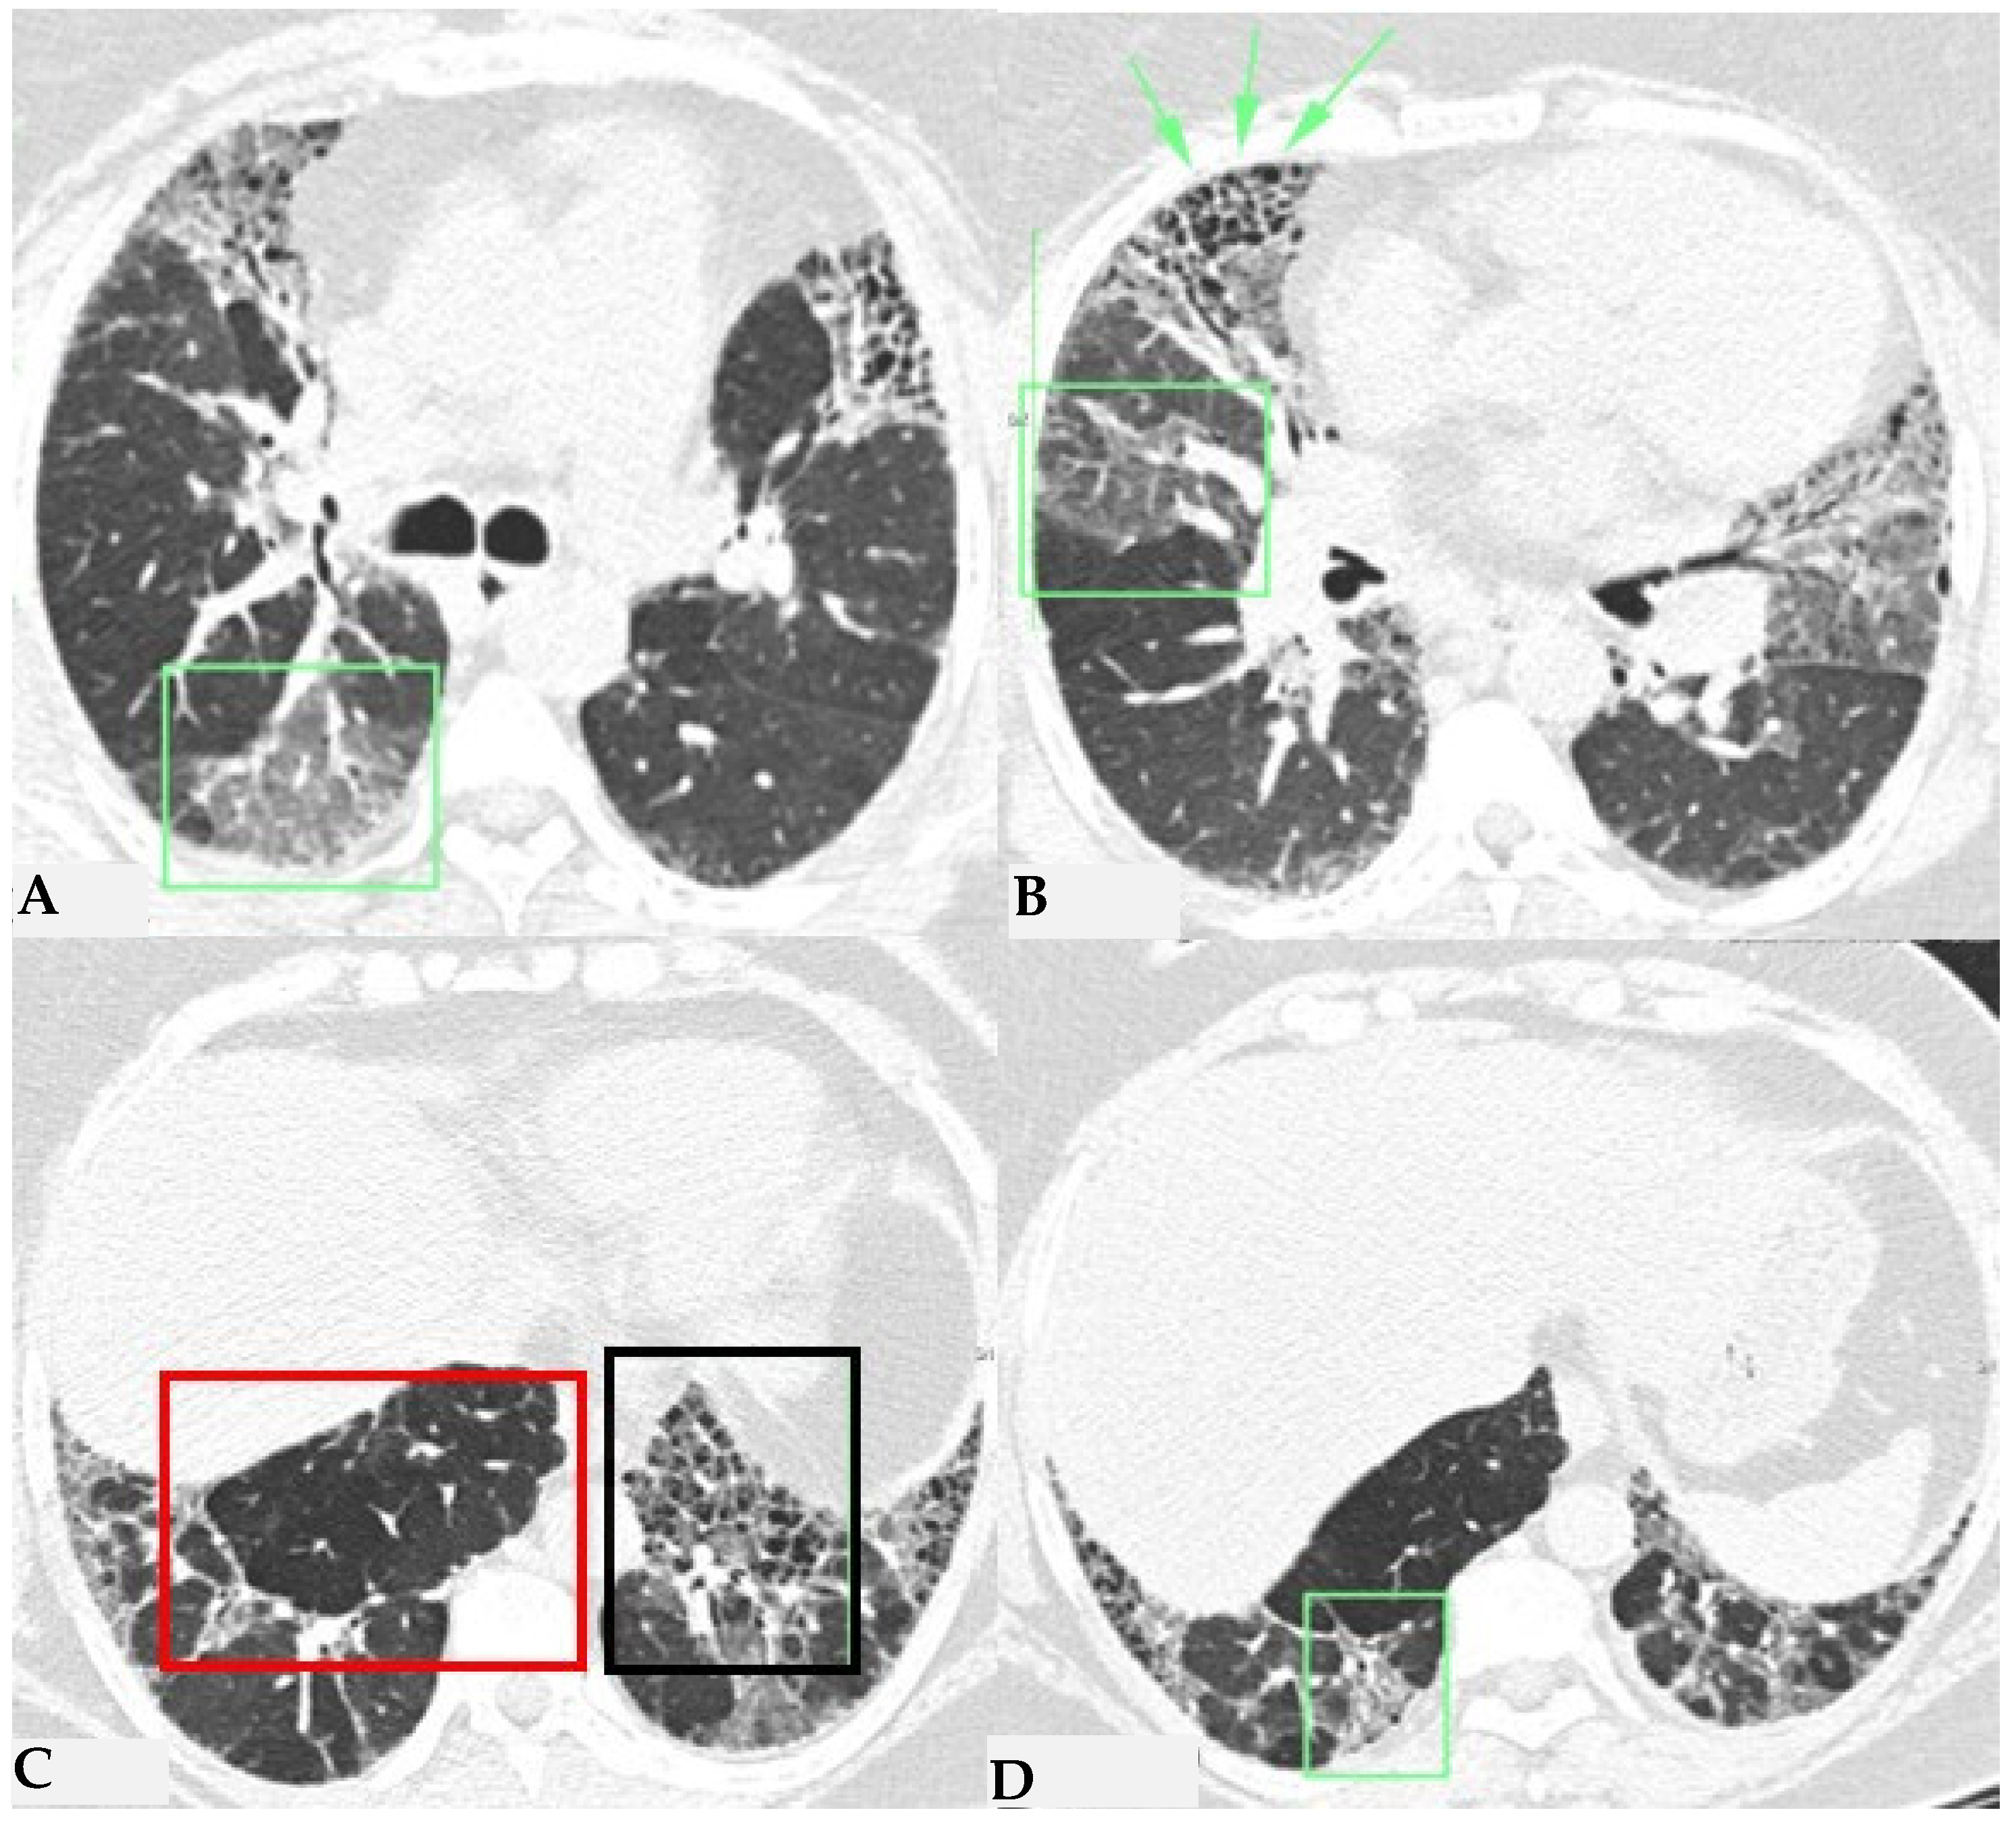

Figure 7.

FHP with small areas of GGO related to acute exacerbation: axial chest HRCT scan. HRCT pattern characterized by mild amorphous GGO components in the upper lobes (red box), predominantly centrally located, with sectoral signs of interface and anterior asymmetric reticulations. Minimal traction bronchiolectasis coexists (A); subcarinal scan reveals GGO with moderate distortion, septal thickening and alterations predominantly bronchocentric in distribution (green box in (B)). The changes exhibit a “patchy” distribution with areas of mosaic attenuation.

Figure 8.

Axial chest HRCT scan. Asymmetric fibrotic alterations with volume loss on the right in the upper lobe (A); in the lower lobes on the right, a significant extensive area of reduced attenuation is evident, suggestive of air trapping (red box), with components of distorted GGO and fibrosing characteristics with intra- and interlobular thickening and traction bronchiectasis/bronchiolectasis (B).